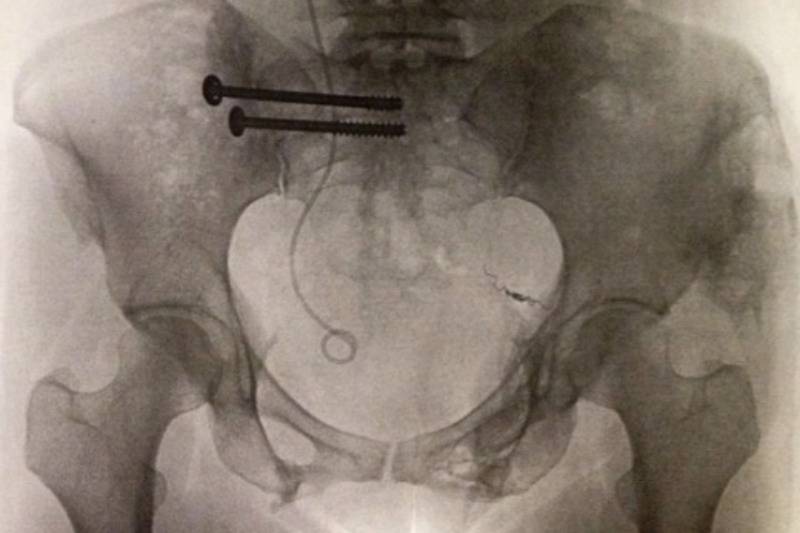

xray of chest with screws

triathloninspires

Despite being in shock, Colleen remembers people rushing to her side and screaming that she was alive. She may have been alive to much of everyone's surprise but barely. Colleen's description of her injuries is quite graphic, so be cautious as you read her next quote:

"I raised my head just enough to see something bright white and yellow protruding from my leg: bone, tendons, and fatty cells. The skin had peeled right off most of the lower half of my body, along with my clothing. There wasn’t any normal flesh to see. My abdomen was opened up, and I was bleeding out."